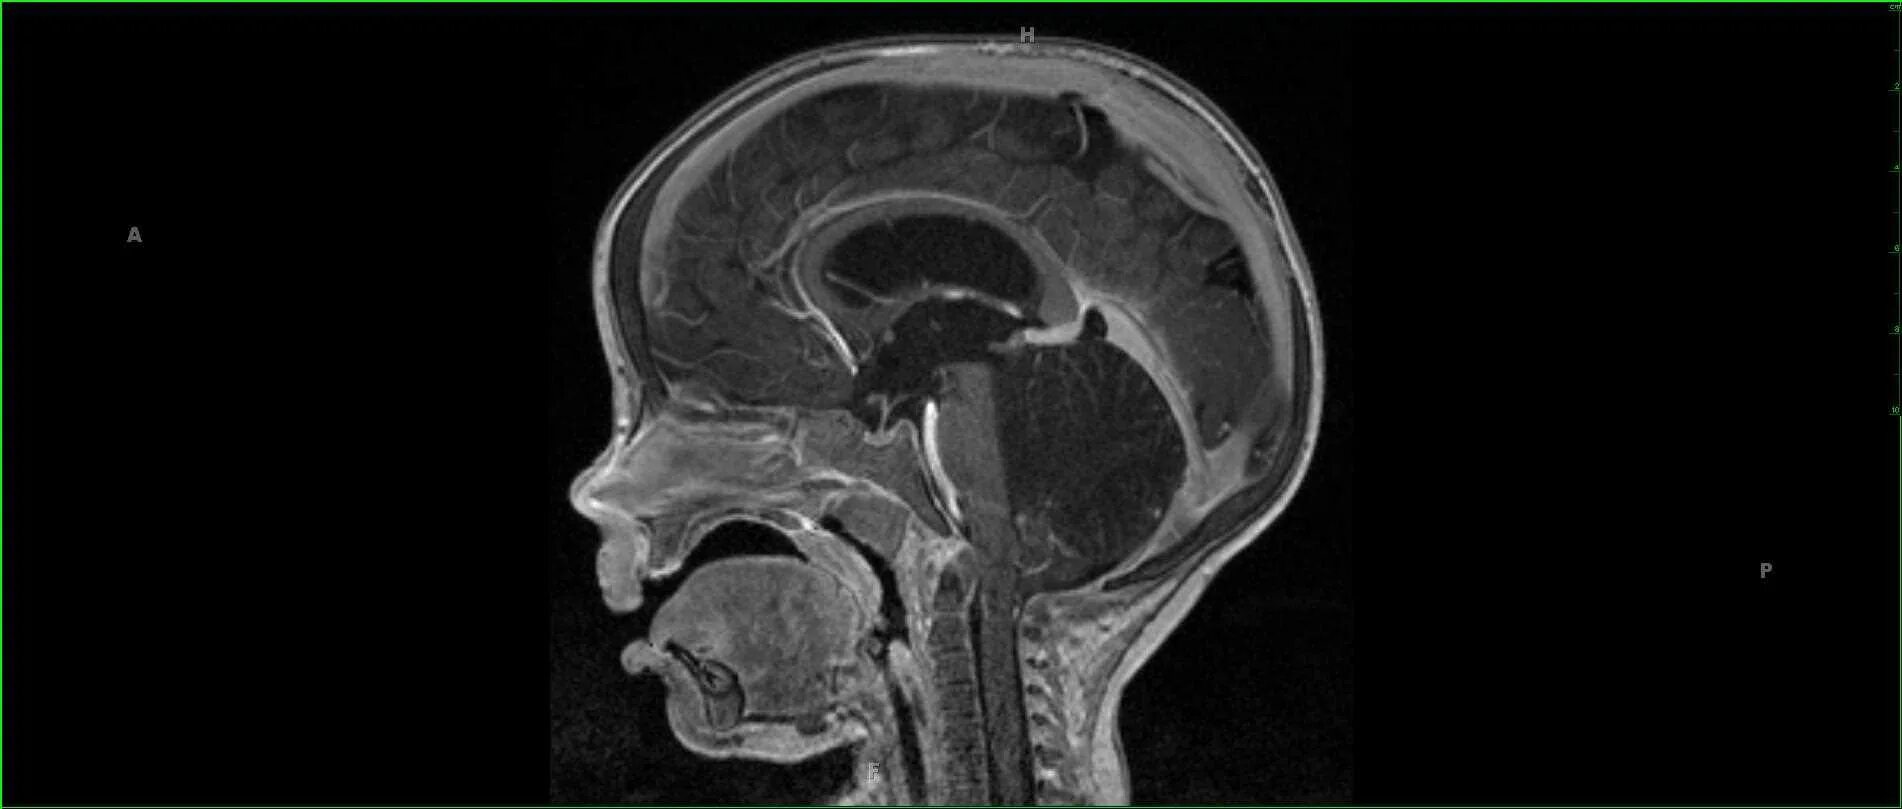

Денди уокера мрт